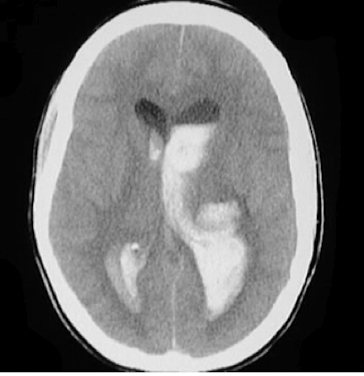

Q

intraventricular